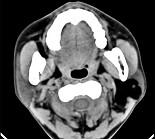

问题 女性,50岁,左侧面部肿胀,CT检查如图,应考虑为()

选项 A.左侧腮腺囊腺瘤 B.左侧腮腺囊肿 C.左侧腮腺脂肪瘤 D.左侧腮腺错构瘤 E.左侧腮腺炎

答案 C